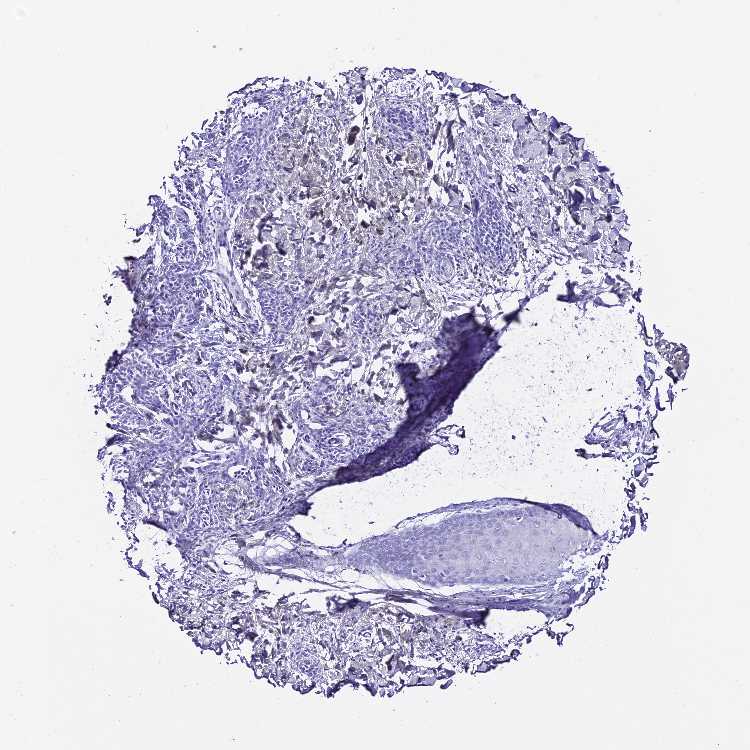

SKIN 1 - Antibody stainingi

Antibody staining in the annotated cell types in the current human tissue is reported as not detected, low, medium, or high, based on conventional immunohistochemistry profiling in selected tissues. This score is based on the combination of the staining intensity and fraction of stained cells.

Each image is clickable and will lead to virtual microscopy that enables deeper exploration of all samples and also displays staining intensity scores, fraction scores and subcellular localization as well as patient and tissue information for each sample.

Antibody HPA045461

Fibroblasts Not detected